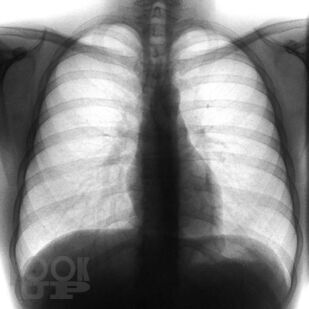

Переработанное и дополненное 3-томное издание «Sobotta. Атлас анатомии человека» является современным учебным пособием. Новое издание атласа отличается от предыдущих клинической направленностью преподавания анатомии: приведено большое количество клинических наблюдений, подтверждающих значение глубоких фундаментальных знаний анатомии при диагностике и лечении различных патологий. Это в полной мере соответствует современным требованиям, предъявляемым к медицинскому образованию, и адаптировано к новым образовательным стандартам. Атлас структурирован по региональному принципу, что соответствует темам учебных сертификационных циклов. Первый том включает разделы общей анатомии, а также подробно иллюстрирует строение костей, их соединений и мышц туловища и конечностей. Упрощенные схемы вводного характера и общие обзоры помогают понять более сложные рисунки и связи. Второй том посвящен анатомии внутренних органов грудной, брюшной полостей и органов таза. В третьем томе представлена анатомия органов головы, шеи, большой раздел посвящен нейроанатомии. Новое издание содержит высококачественные иллюстрации, дополненные подробными подрисуночными подписями. Оригинальные рисунки сопровождаются современными изображениями, полученными с помощью компьютерной и магнитно-резонансной томографии, ультразвуковых и эндоскопических методов исследования, а также интраоперационными цветными фотографиями внутренних органов и т.д. К атласу прилагаются таблицы, содержащие краткую систематизированную информацию об анатомии и о функциях мышц, суставов и об их иннервации. Использование в атласе трехъязычной терминологии повышает интерес к нему со стороны иностранных студентов, обучающихся медицине в России.